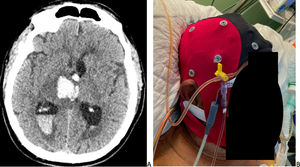

Our patient, a 67-year-old man with arterial hypertension and diabetes mellitus, was admitted to the ICU due to focal seizures and altered level of consciousness secondary to right intracranial haematoma with intraventricular extension (Fig. 1A). The patient presented hydrocephalus, requiring EVD placement following sedation and orotracheal intubation. An EEG was requested to rule out non-convulsive status epilepticus. The study was performed under the supervision of a neurosurgeon to ensure correct manipulation of the EVD, using an EEG cap with electrodes placed according to the international 10–20 EEG system (VIASYS Nicolet NicVue 2.9; Middleton, WI, USA) (Fig. 1B).